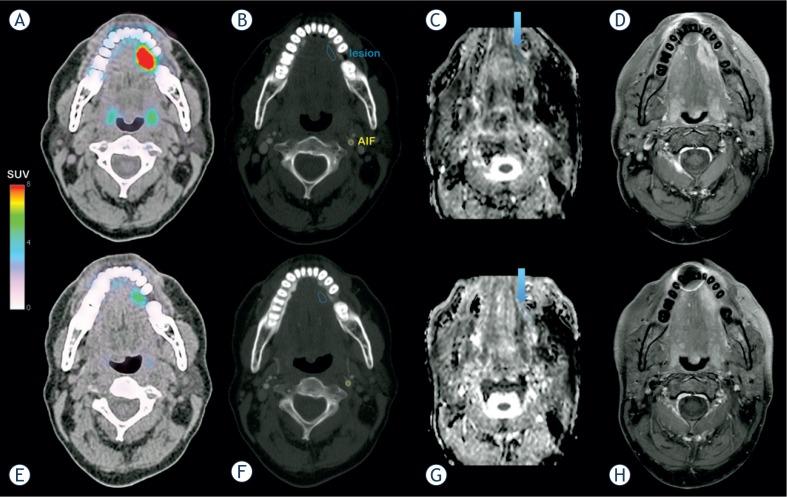

Cetuximab, a monoclonal antibody targeting the Epidermal Growth Factor Receptor (EGFR), has demonstrated activity in various tumor types. Using dynamic contrast-enhanced computed tomography (DCE-CT), we investigated the early activity of cetuximab monotherapy in previously untreated patients with squamous cell carcinoma of the head and neck (SCCHN).

Treatment-naïve patients with SCCHN received cetuximab for 2 weeks before curative surgery. Treatment activity was evaluated by DCE-CT at baseline and before surgery. Tumor vascular and interstitial characteristics were evaluated using the Brix two-compartment kinetic model. Modifications of the perfusion parameters (blood flow Fp, extravascular space ve, vascular space vp, and transfer constant PS) were assessed between both time points. DCE data were compared to FDG-PET and histopathological examination obtained simultaneously. Plasmatic vascular markers were investigated at different time points.

Fourteen patients had evaluable DCE-CT parameters at both time points. A significant increase in the extravascular extracellular space ve accessible to the tracer was observed but no significant differences were found for the other kinetic parameters (Fp, vp or PS). Significant correlations were found between DCE parameters and the other two modalities. Plasmatic VEGF, PDGF-BB and IL-8 decreased as early as 2 hours after cetuximab infusion.